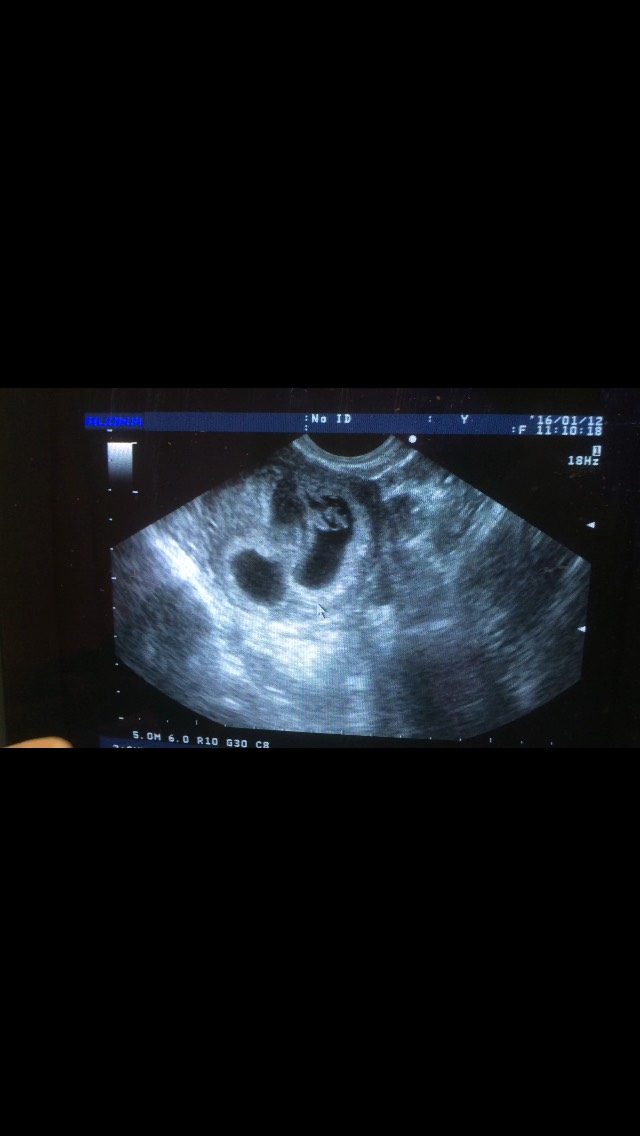

现在没有出血了,每天除了上班时间,下班回到家除了吃饭和洗手间,其余时间都卧床。b超提示宫腔还有很多积血(左上),一胎停止发育(左下),一胎暂时还可以(右)。心里觉得可能是出血压在停止发育那个宝宝那令他没养分供应而失去它的。